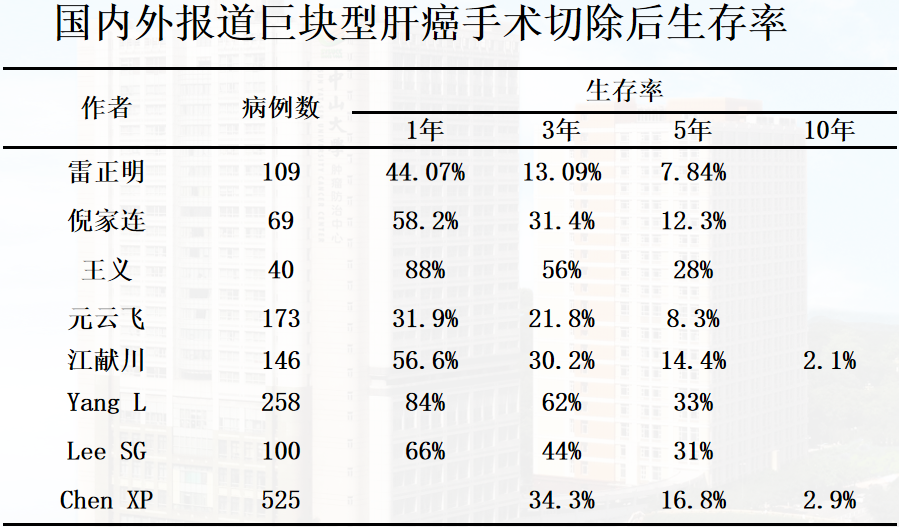

原发性肝癌能手术切除者仅占10%~15%,由于巨块型肝癌多数合并血管侵犯和肝内播散以及肝功能不全,手术切除危险性和难度更大,手术切除率更低,只能进行姑息性切除。Taniai N报道≥10cm的肝癌术后生存率明显低于<10cm的肝癌。

梁力建等比较了巨块型肝癌的切除组(68例)以及非切除组(35例)生存率。巨块型肝癌切除组与非切除组生存率有显著差异(P<0.05)。